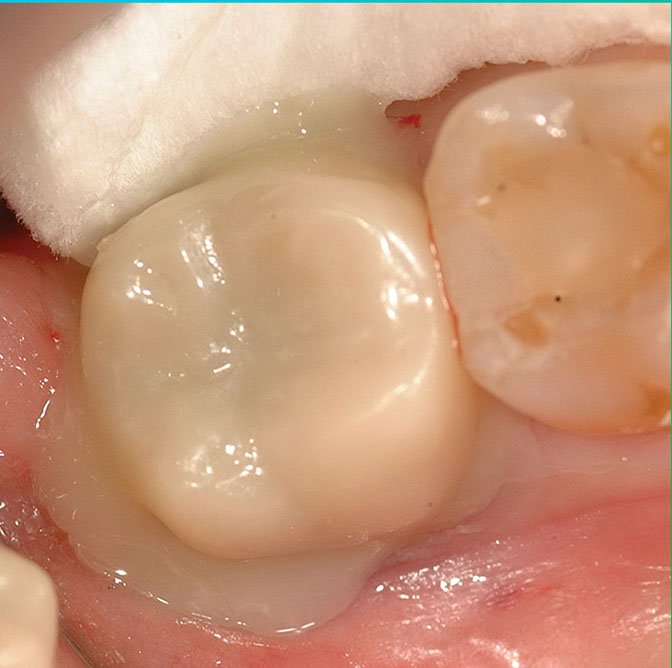

Sintered polished - note lower value.